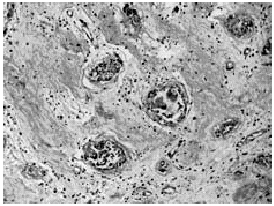

En la autopsia, se encontraron 3000 mL de ascitis serohemática. El corazón era de tamaño y peso normal. En la aurícula izquierda había una lesión exofítica, que ocupaba aproximadamente el 70% de la cavidad y midió 3 × 2,5 × 2,3 cm, era papilar, de consistencia blanda, color blanco grisáceo y se encontraba adherida a la pared medial por un pedículo de 0,3 × 0,2 × 0,1 cm (Fig. 1). Microscópicamente se identificó una neoplasia de aspecto mixoide, poco celular, mezclada con glándulas, las cuales se encontraron en aproximadamente 20% del tejido examinado. Las glándulas estaban formadas por epitelio cúbico, con núcleos pequeños, ovoides, de localización basal, con escasas células caliciformes. Con las tinciones de PAS (Fig. 2) y hierro coloidal se demostró positividad para mucosubstancias. El resto de la lesión estaba constituida por células fusiformes o estelares, inmersas en una matriz mixoide. De forma aislada, había macrófagos con hemosiderina y células gigantes multinucleadas. Las reacciones de inmunohistoquímica en el componente glandular resultaron positivas para antígeno carcinoembrionario y citoqueratina 7 y negativas para Hepat y a-fetoproteína (Fig. 3).

Fig. 2. Aspecto microscópico del mixoma que muestra elementos glandulares y estroma mixoide. PAS 100x.